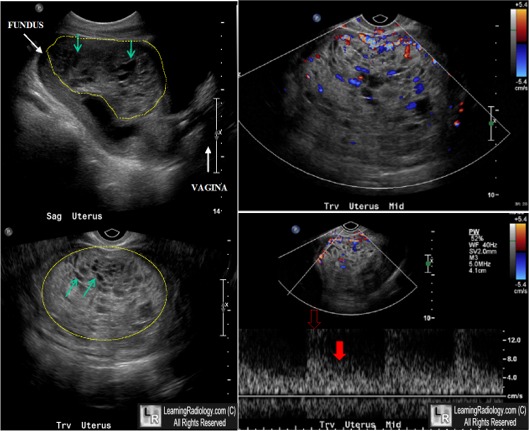

LearningRadiology - Hydatidiform, Mole, Molar, Pregnancy, Ultrasound

LearningRadiology - Hydatidiform, Mole, molar, pregnancy, ultrasound www.learningradiology.com

molar pregnancy ultrasound mole hydatidiform radiology complete findings learningradiology here these arrows same without click cow us